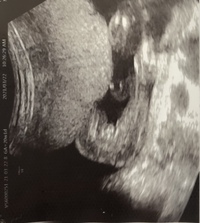

妊娠週目の2D画像。 横になった姿勢で、顔のアップの左側に写っている顎の細さが分かりました。 赤ちゃんの推定体重345g。 私の腹囲は人生初の90cm台になり、どこからみても貫禄充分なお母さんでした。 命の始まりは神秘的! 2D・3D・4Dのエコー写真で妊娠週0日(w0d)の超音波(エコー)写真 妊娠も折り返し地点。 経過はいたって順調。何も見えないので女の子の可能性が高いですね、との事。 父ちゃんも母さんも、元気ならどっちでもいーから、すくすくお腹の中で育つんだぞ~主人曰く「先生は女の子でまちがいないとも言っていたよ」とのこと。 妊娠週赤ちゃんのエコー写真・超音波写真まとめ ママライターのみなさんの妊娠出産体験談から妊娠週の赤ちゃんのエコー写真を集めました。